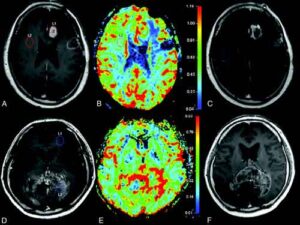

Una terapia multipla sembra essere efficace nell’aumentare la sopravvivenza al glioblastoma, un grave tumore del cervello.

L’esperimento, finora eseguito solo sulle cavie, e’ stato realizzato da un gruppo di ricercatori del Johns Hopkins Kimmel Cancer Center ed e’ stato pubblicato sulla rivista PLOS One.  La terapia multipla prevede due tipi di immunoterapia e uno di radioterapia. Le cavie trattate con questo triplo approccio sono sopravvissute 67 giorni, mentre quelle che avevano ricevute le sole immunoterapie sono sopravvissute solo 24 giorni. Nessuno dei trattamenti utilizzati e’ di nuova concezione. La novita’ consiste solo nell’uso combinato. ”Stiamo cercando solo di trovare – ha spiegato Charles Drake, principale autore della ricerca – il giusto bilanciamento tra strategie di lotta per questo tipo di tumore”.